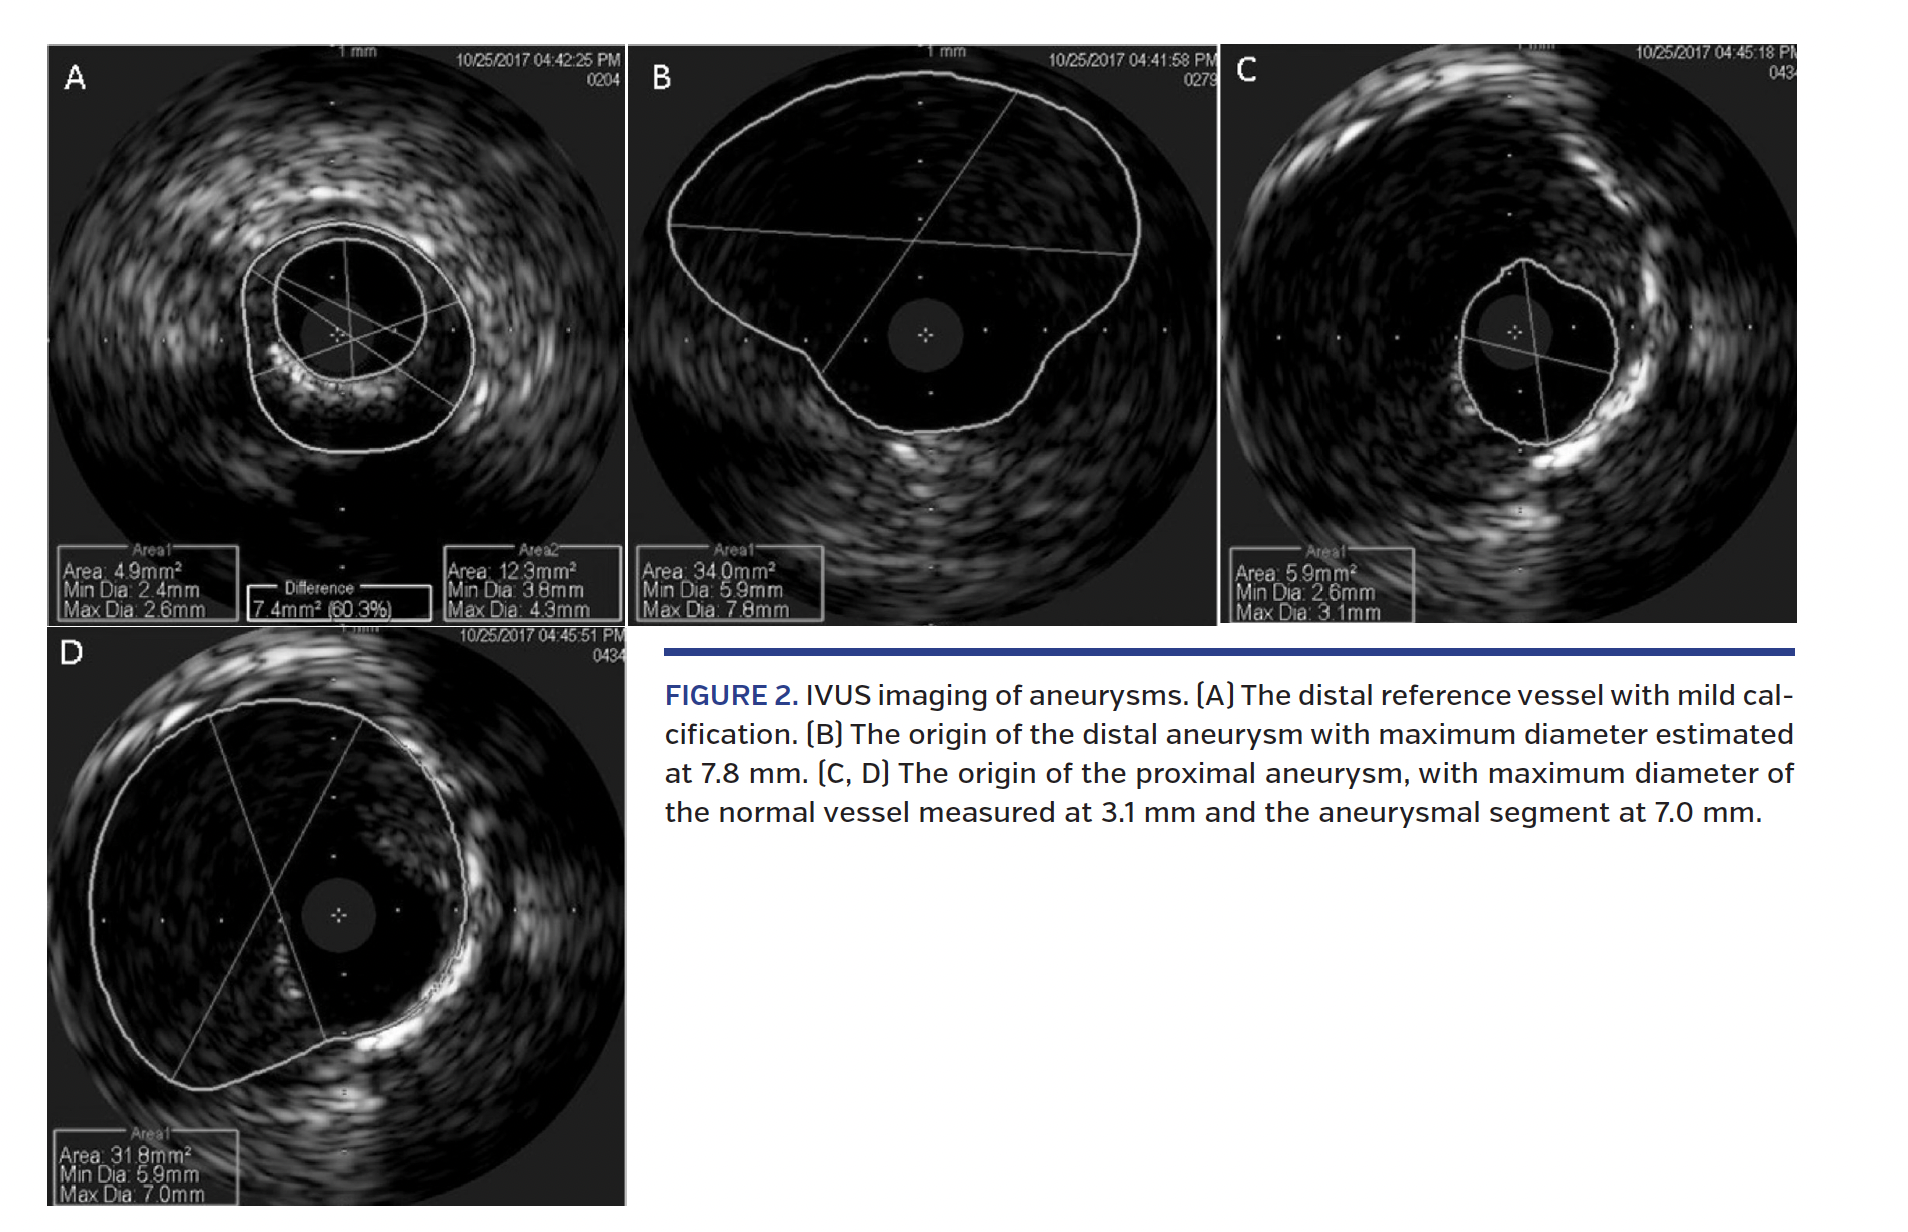

After engaging the RCA with an AL guide catheter, an 8 Fr GuideLiner (Vascular Solutions) was placed for additional support. IVUS was performed, revealing distal aneurysm with maximal diameter of 7.8 mm and proximal aneurysm with maximal diameter of 7.0 mm (Figure 2; Video 3). Predilation was performed with a 2.5 x 40 mm Apex balloon (Boston Scientific) at 12 atm. A 2.75 x 38 mm Synergy stent (Boston Scientific) was placed at 14 atm across the distal part of the second aneurysm into the posterolateral branch of the RCA. We then stented from the distal to proximal RCA with three 4.0 x 38 mm Synergy stents (inflated at 11, 18, and 12 atm, respectively), sparing the ostium. Notably, following this initial stenting, the proximal aneurysm appeared successfully excluded, although the distal aneurysm continued to show blood flow. Using the stent balloon, we then tracked the GuideLiner to the distal RCA (Figure 3A; Video 4). Through the GuideLiner, we passed a 4.0 x 19 mm GraftMaster into the distal aneurysm and inflated at 16 atm (Figure 3B; Video 5). The aneurysm was still not completely excluded, so an additional 4.0 x 16 GraftMaster was placed at 18 atm proximal to the prior covered stent, resulting in successful exclusion of aneurysmal blood flow (Figure 3C; Video 6). We then postdilated the posterolateral branch stent with a 3.5 x 27 mm non-compliant (NC) balloon at 18 atm. Subsequent postdilations to the remaining RCA stents were performed with a 4.5 x 20 mm NC balloon using inflations ranging from 14-18 atm. Lastly, we stented the ostial RCA with a 4.0 x 18 mm Xience stent (Abbott Vascular), and postdilated with a 4.5 x 20 mm NC balloon at 14 atm, with good final angiographic result (Figure 3D; Video 4). The patient was discharged the following day with plans for at least 1 year of aspirin and clopidogrel.